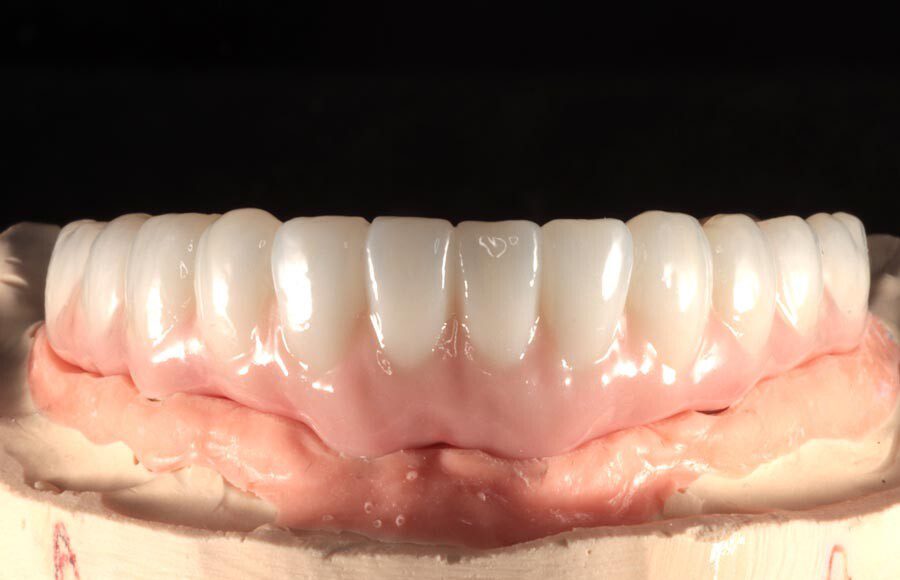

Once the final design is approved, the lab begins fabricating definitive restorations. They are able to add a lot more character and definition at this stage, resulting in restorations that are beautiful and realistic.

More importantly, special care is taken to ensure the tissue-fitting surfaces are smooth and convex. This ensures that any plaque that builds up here is easily removed with regular brushing and water-picking. Hygiene is important for long-term tissue health and this implant success.